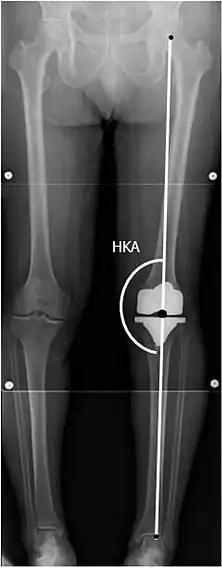

Angles commonly measured before knee replacement surgery:

• Hip-knee-shaft angle (HKS)[10]

• Hip-knee-ankle angle (HKA)[11]

To indicate knee replacement in case of osteoarthritis, its radiographic classification and severity of symptoms both should be substantial. Such radiography should consist of weightbearing X-rays of both knees: AP, lateral, and 30 degrees of flexion. AP and lateral views may not show joint space narrowing, but the 30-degree flexion view is most sensitive for narrowing. Full-length projections also are used in order to adjust the prosthesis to provide a neutral angle for the distal lower extremity. Two angles used for this purpose are:

• Hip-knee-shaft angle (HKS),[10] an angle formed between a line through the longitudinal axis of the femoral shaft and its mechanical axis, which is a line from the center of the femoral head to the intercondylar notch of the distal femur.[12]

• Hip-knee-ankle angle (HKA),[11] which is an angle between the femoral mechanical axis and the center of the ankle joint.[12] It is normally between 1.0° and 1.5° of varus in adults.[13]